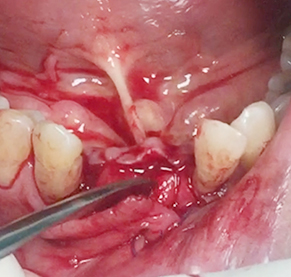

Horizontal ridge augmentation

Vertical ridge augmentation